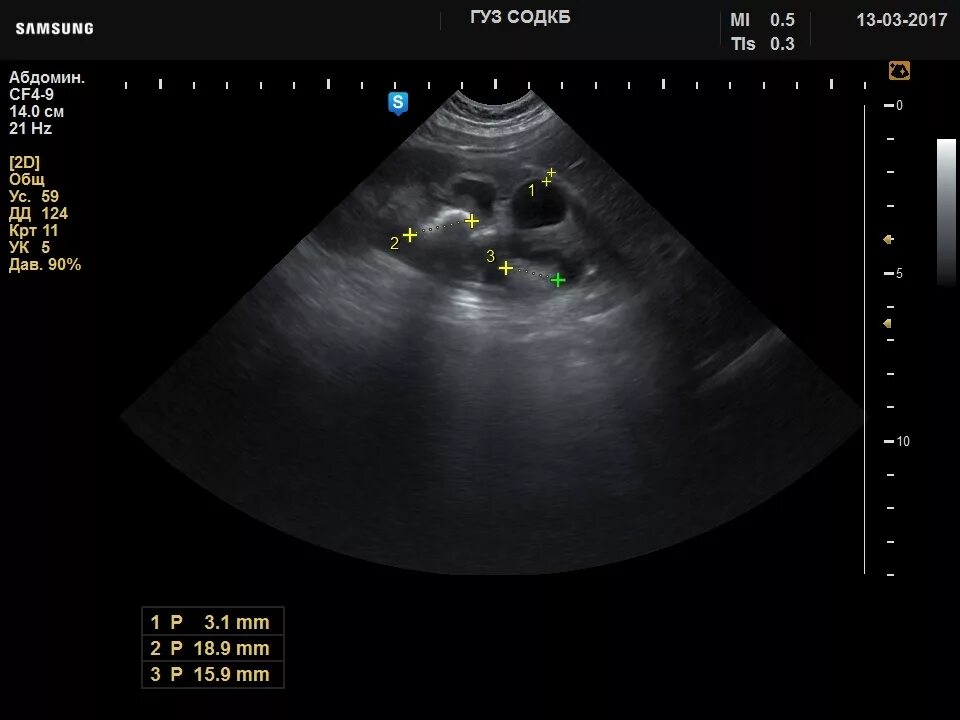

Узи нервов сделать в москве